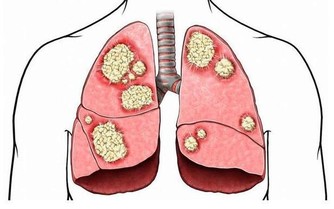

病從入口,相信大家都知道這個道理。再加上現在生活條件變好了,我們每天吃的食物也越來越豐富,各種各樣的美食應接不暇。但是,隨之也帶來了健康問題,其中,痛風就是比較嚴重的問題,而導致痛風的就是尿酸過高,今天,隨小編來學習一下怎麼降尿酸吧。

一、尿酸高?多半是“吃”出來的,身體出現這些表現,可能是痛風了